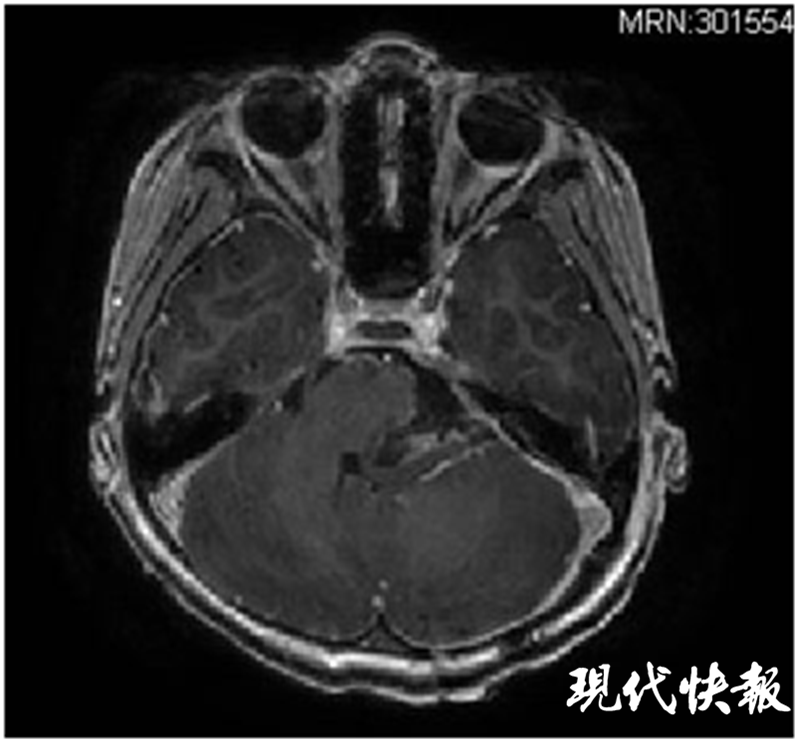

△術(shù)后核磁共振顯示腫瘤全切,腦干復(fù)位

手術(shù)團(tuán)隊(duì)在術(shù)前反復(fù)討論,制定了最佳的手術(shù)方案,并對(duì)手術(shù)中可能出現(xiàn)的各種緊急狀況做了充分準(zhǔn)備。麻醉師、護(hù)士時(shí)刻監(jiān)測(cè),保證了患兒生命體征始終平穩(wěn)。最終,歷時(shí)6個(gè)多小時(shí)的手術(shù),不但成功將諾諾腦內(nèi)的腫瘤完全切除,而且保留了腫瘤周圍所有正常的血管和神經(jīng)。

術(shù)后經(jīng)過(guò)一段時(shí)間調(diào)理,諾諾很快就能下地活動(dòng),頭痛和嘔吐的癥狀也都消失了。